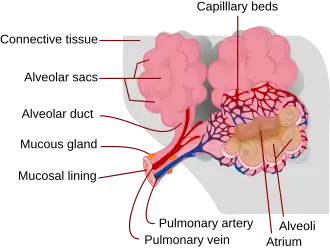

Respiratory zone

The conducting zone of the respiratory tract ends at the terminal bronchioles when they branch into the respiratory bronchioles. This marks the beginning of the terminal respiratory unit called the acinus which includes the respiratory bronchioles, the alveolar ducts, alveolar sacs, and alveoli.[27] An acinus measures up to 10 mm in diameter.[28] A primary pulmonary lobule is the part of the lung distal to the respiratory bronchiole.[29] Thus, it includes the alveolar ducts, sacs, and alveoli but not the respiratory bronchioles.[30]

The unit described as the secondary pulmonary lobule is the lobule most referred to as the pulmonary lobule or respiratory lobule.[25]: 489 [31] This lobule is a discrete unit that is the smallest component of the lung that can be seen without aid.[29] The secondary pulmonary lobule is likely to be made up of between 30 and 50 primary lobules.[30] The lobule is supplied by a terminal bronchiole that branches into respiratory bronchioles. The respiratory bronchioles supply the alveoli in each acinus and is accompanied by a pulmonary artery branch. Each lobule is enclosed by an interlobular septum. Each acinus is incompletely separated by an intralobular septum.[28]

The respiratory bronchiole gives rise to the alveolar ducts that lead to the alveolar sacs, which contain two or more alveoli.[20] The walls of the alveoli are extremely thin allowing a fast rate of diffusion. The alveoli have interconnecting small air passages in their walls known as the pores of Kohn.[20]

Respiratory tract

The lower respiratory tract is part of the respiratory system, and consists of the trachea and the structures below this including the lungs.[32] The trachea receives air from the pharynx and travels down to a place where it splits (the carina) into a right and left primary bronchus. These supply air to the right and left lungs, splitting progressively into the secondary and tertiary bronchi for the lobes of the lungs, and into smaller and smaller bronchioles until they become the respiratory bronchioles. These in turn supply air through alveolar ducts into the alveoli, where the exchange of gases take place.[32] Oxygen breathed in, diffuses through the walls of the alveoli into the enveloping capillaries and into the circulation,[20] and carbon dioxide diffuses from the blood into the lungs to be breathed out.